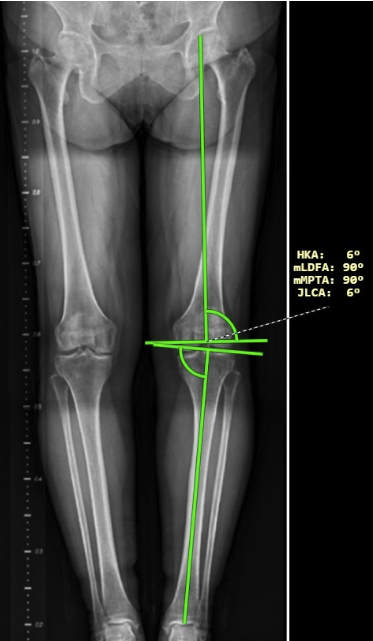

- Lower limb angle measurements have been modified in this version of the DICOM viewer and now also show laterality angles. The laterality of the angles can be determined using the right sidebar in the “Measurement toolset”, drop-down menu ‘Laterality’ in the “Lower limb angles” tab. After measuring the lower limb angles, the following angles are displayed:

- HKA – hip-knee-ankle angle

- mLDFA – mechanical lateral distal femoral angle

- mPTA – medial proximal tibial angle

- JLCA – joint line convergence angle